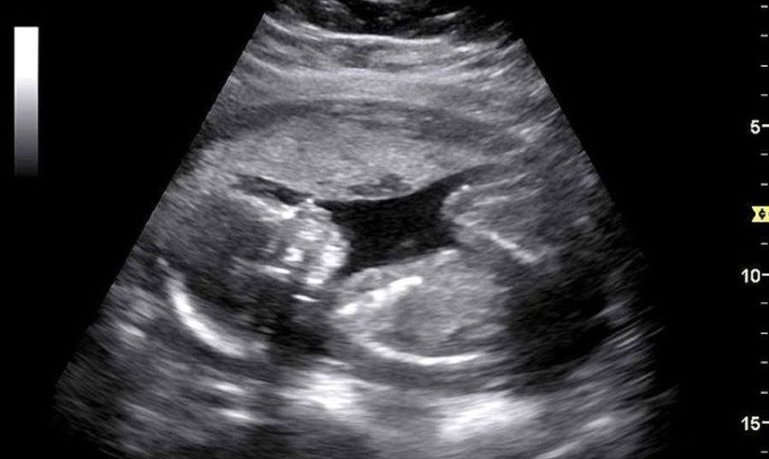

The midwife slowly moved the wand across my stomach, smearing the cold goo back and forth. I resolutely pursed my lips, unable to look anywhere but the tiled ceiling.

“Strong heartbeat!” she smiled as I realized I’d been clinching my fists so tightly my nails left marks on my palms.

This. This was a routine part of my visits. She would do a quick check for my son’s heartbeat. I would flex every muscle in my body and prepare for the worst news possible.